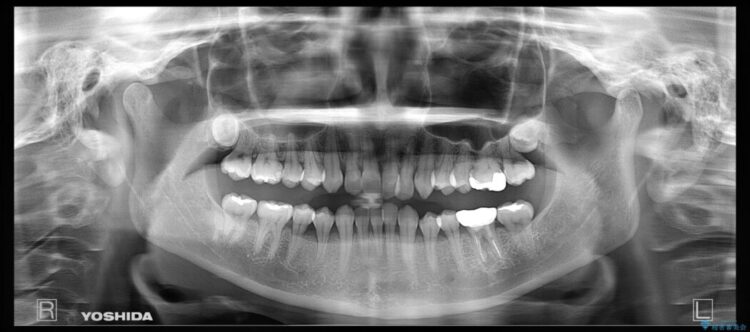

治療計画を立てる上で詳しく精密検査をしたところ、左下の6番目の歯につきまして治療が必要な状態であることが分かり、かぶせ物を外し、内部を確認しました。

結果としては深い部分で根が破折してしまっていました。

破折の処置としては基本的に抜歯が選ばれます。

悪くなっている歯の放置はできないと判断しましたので、患者様と様々な治療プランを相談した上で、最終的に該当の歯は抜歯をして噛み合わせを改善し、その後インビザラインでの矯正治療を行うこととしました。

治療前の精密検査について

当院では矯正治療をご希望される患者様には治療前に必ず精密検査を受けていただいております。

患者様本人に自覚のない状態であっても隠れて歯周病が進行していたり、根幹治療が必要になるといったケースがあります。